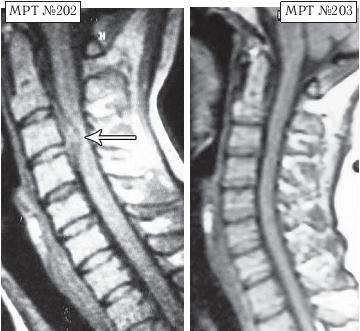

МРТ № 1

На магнитно-резонансной томографии (МРТ) № 1 — шейный отдел позвоночника, в относительно нормальном состоянии.

Шейный отдел позвоночника должен иметь нормально выраженный физиологический лордоз, не должно быть гиполордоза или гиперлордоза, а так же кифотических деформаций.

МРТ № 2

На МРТ № 2 — грудной отдел в состоянии «норма»

Грудной отдел должен иметь нормальную степень кифоза (угол кифоза по Stagnara формируется линией, параллельной замыкательным пластинкам ТIII и ТXI= 25°). Позвоночный канал на грудном уровне имеет округлую форму, что делает эпидуральное пространство узким почти по всей окружности дурального мешка (0,2–0,4 см), а на участке между TVI и ТIX он наиболее узок. Сагиттальный размер: ТIХI = 13–14 мм, ТXII = 15 мм. Поперечный диаметр: > 20–21 мм.